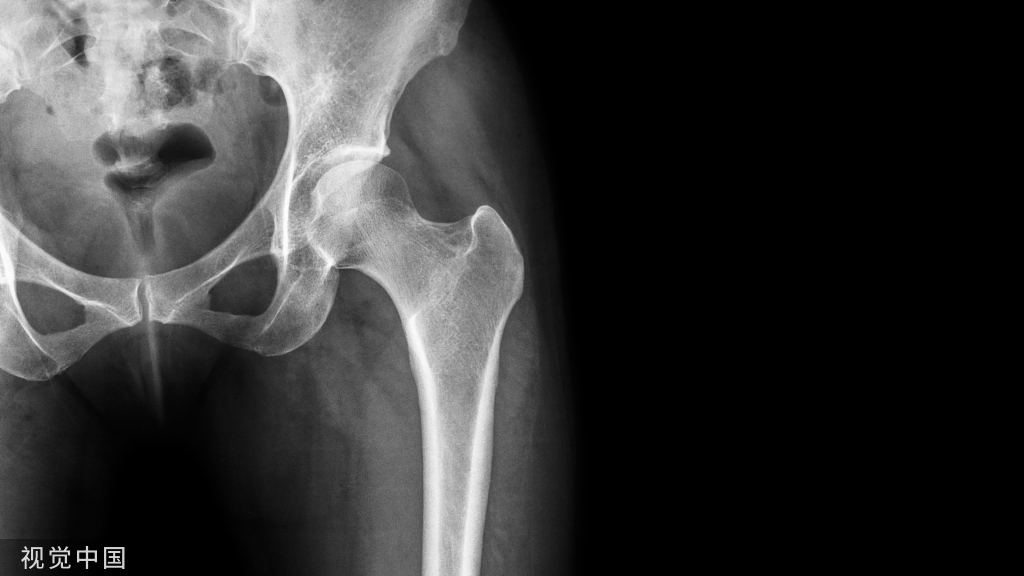

髋关节后脱位影像图。左图示全髋置换术后髋关节脱位,右图示创伤性髋关节后脱位,伴有髋臼后壁骨折